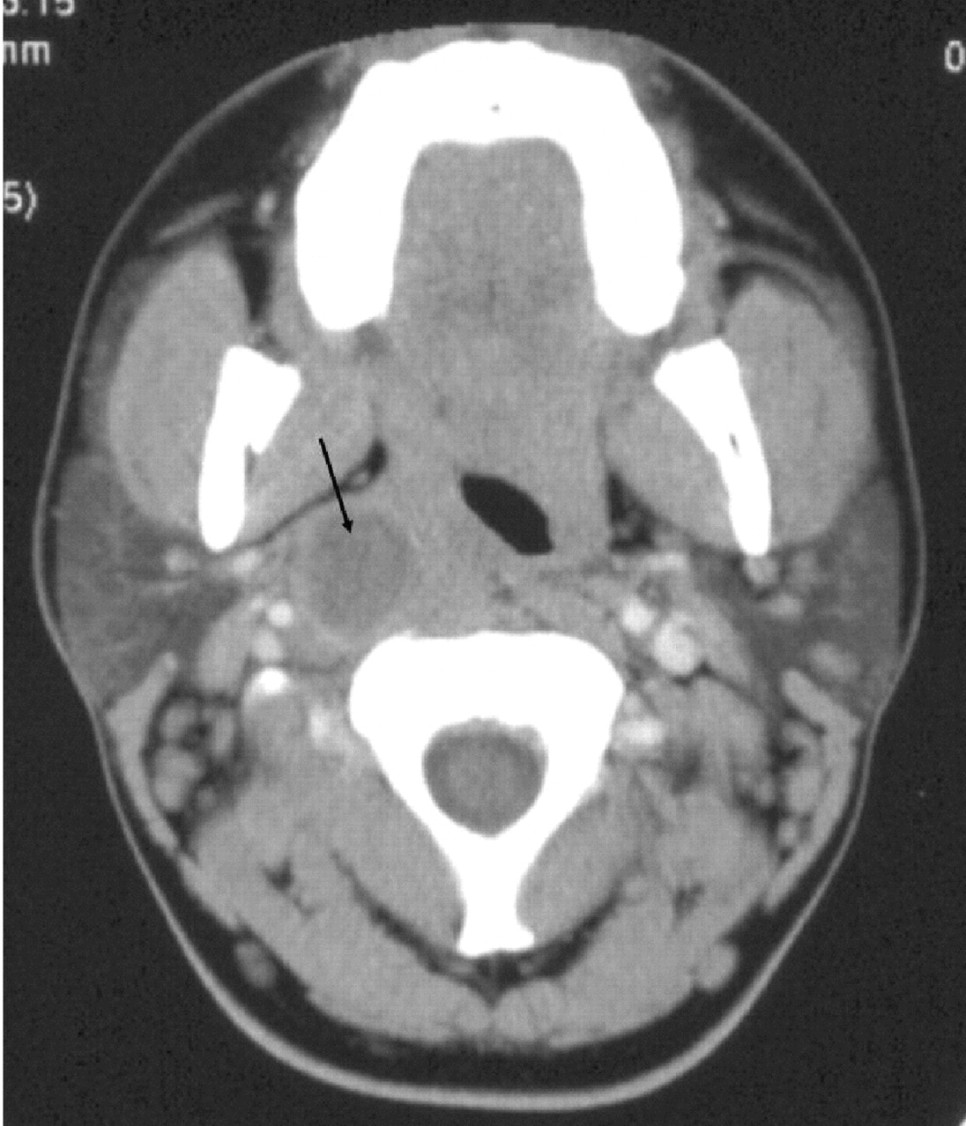

일반적으로 편도 주위 농양에 대한 진단은 보통 임상적으로 실시가 됩니다. 진찰 시 정상으로 보일 수도 있지만, 편도가 안쪽으로 전위되어 목젖이 반대쪽으로 밀립니다. 일방성으로 인해 위턱 등이 붓는 경우도 있고, 때로는 기도 폐색을 일으킬 수도 있습니다. 편도 주위 농양은 심해지면 외부의 인두 공간이나 경동맥을 싸고 있는 막까지 파급될 수 있습니다. 편도 주위의 봉와직염으로 농양으로 오인될 수 있으므로 CT 촬영에서 감별을 해야 합니다.

편도 주위 농양 절개 배농술=편도 주위 농양 시의 위치가 파악되면 마취를 해서 절개 후에 고름을 짜냅니다.부인두 농양부 인두 공간은 편도를 둘러싼 공간인 상인두 수축근을 빠져나와 옆으로 침범했을 경우 생기는 농양입니다. 성인에서는 치성 감염에 의한 부인 두농양이 많지만, 소아에서는 편도염 합병증이 되는 경우가 많습니다. 증상은 편도주위농양과 거의 같으나 더 넓어지는 상태에서 척추주위근육까지 침범하여 경부에 경직될 수 있으며 경동맥막을 따라 종격동까지 갈 수 있는 것으로 알려져 있습니다. 임상적으로 편도 주위 농양과 혼동될 수 있어 조영제를 사용한 CT 촬영이 필요합니다.

편도선에서 더 나아가 상인두 수축근을 지나가면 바로 안쪽 인두 농양이 됩니다. CT를 실시하여 감별진단이 이루어집니다.